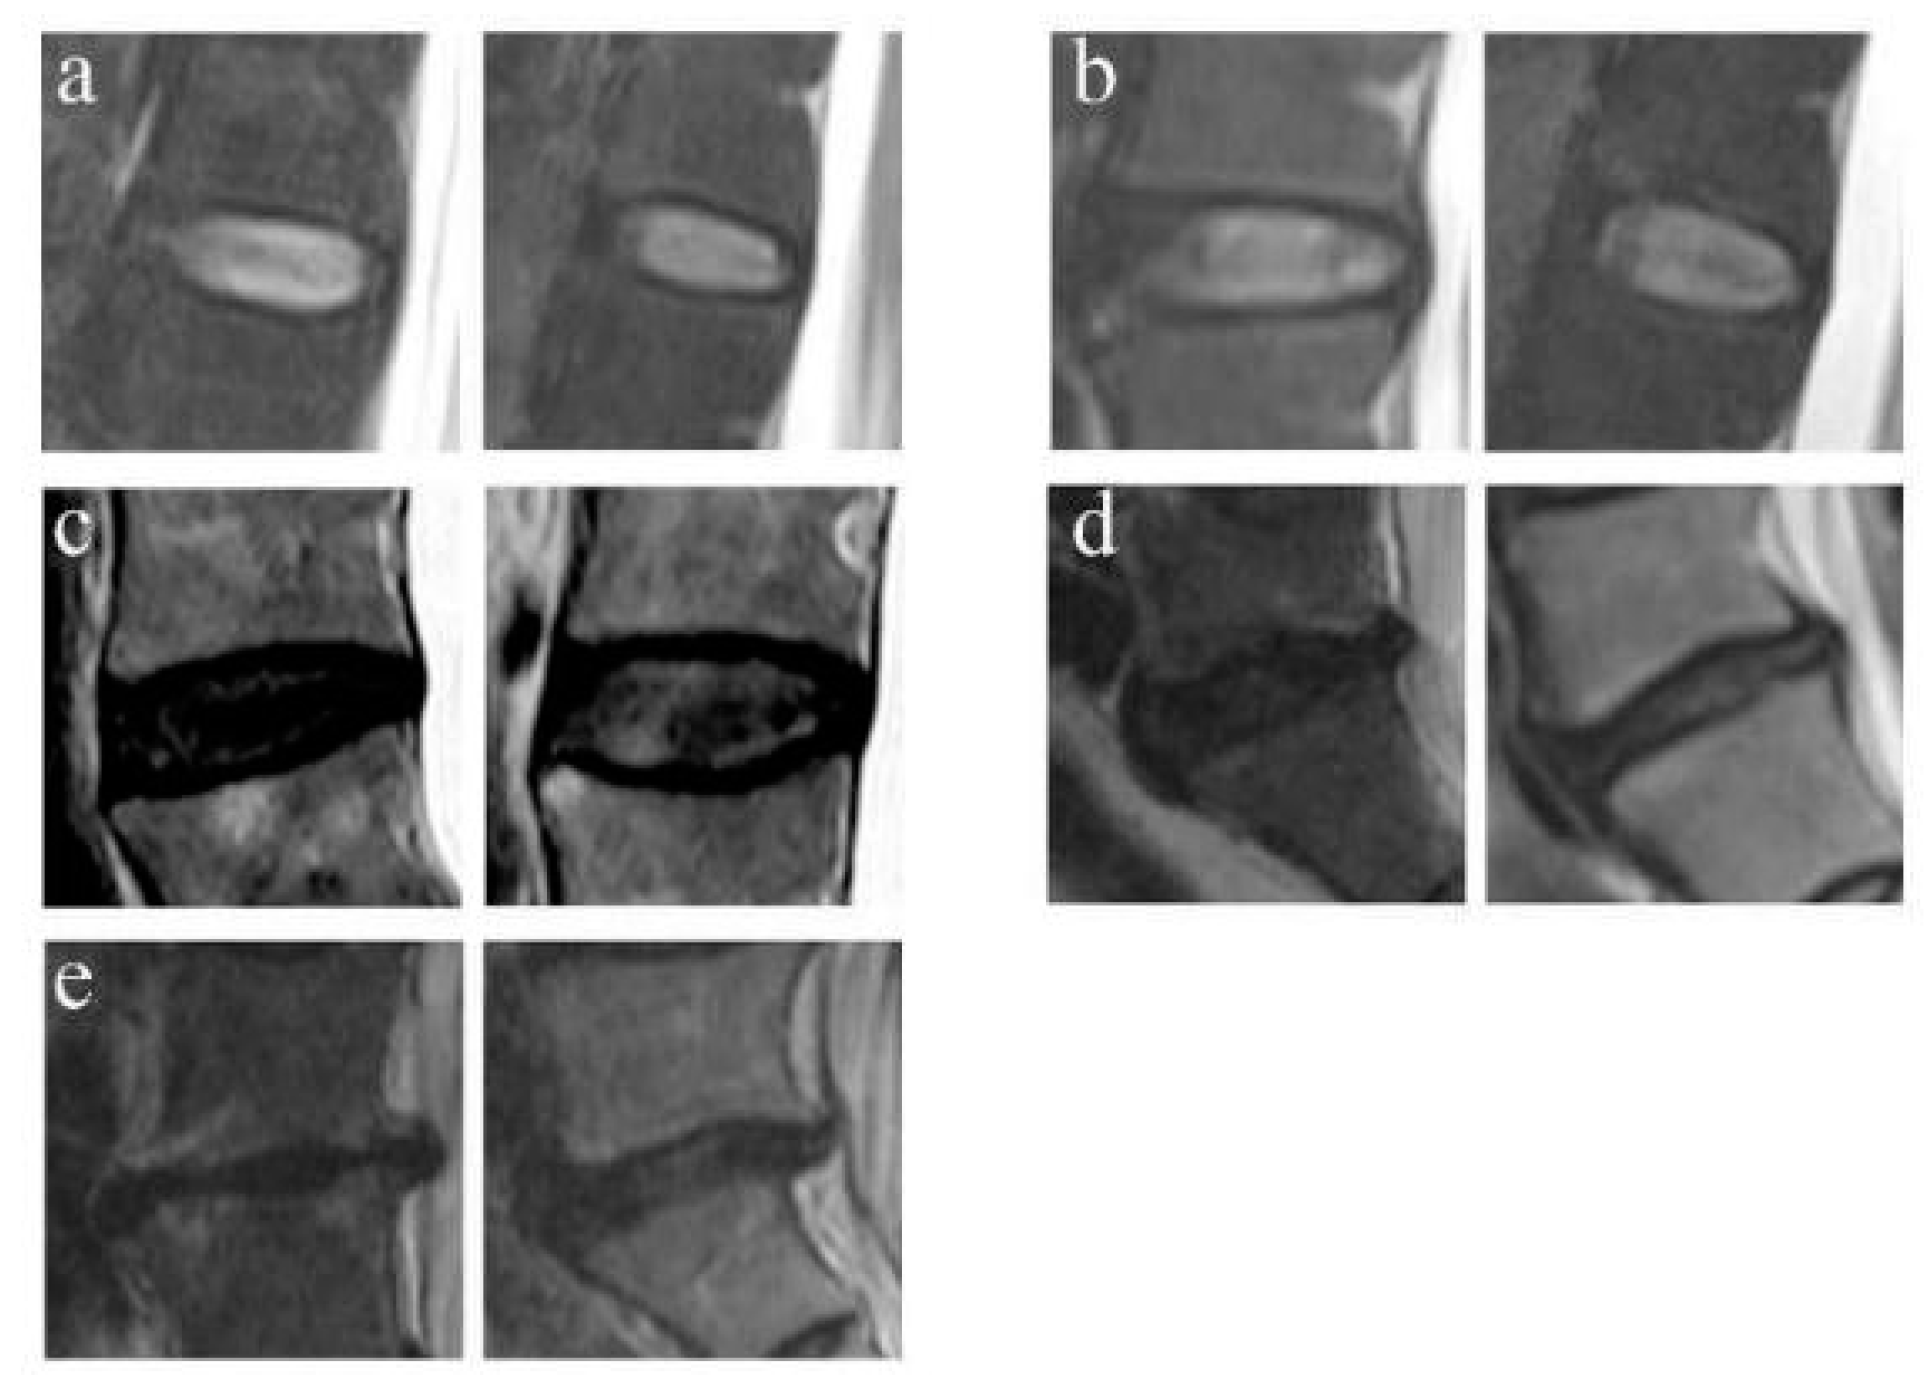

The LDD was classified into 5 grades by using the criterion of Pfirrmann et al. on T2-weighted MRI [9]. Grade 1 corresponds to a normal disc and grade 5 corresponds to a terminal degenerative disc (Figure 2).

Figure 2.

Example of Pfirrmann grades for the LDD. (a) Grade Ⅰ: normal discs. (b) Grade Ⅱ: the mild degeneration discs with structure inhomogeneous with/without horizontal bands. (c) Grade Ⅲ: the moderate degeneration discs with gray structure, can not distinguish the nucleus and annulus, intermediate signal intensity, and normal/slightly decreased disc height. (d) Grade Ⅳ: the severe degeneration disc with gray/black structure, the distinction of nucleus and annulus is lost, intermediate/hypointense signal intensity, and normal/moderately decreased disc height. (e) Grade Ⅴ: End-stage degeneration disc with black structure, the distinction of nucleus and annulus is lost, hypointense signal intensity, and collapsed disc space.